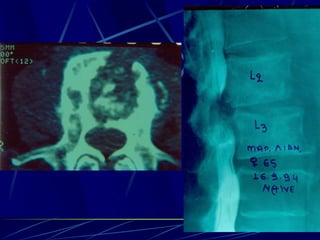

Brucella melitencis